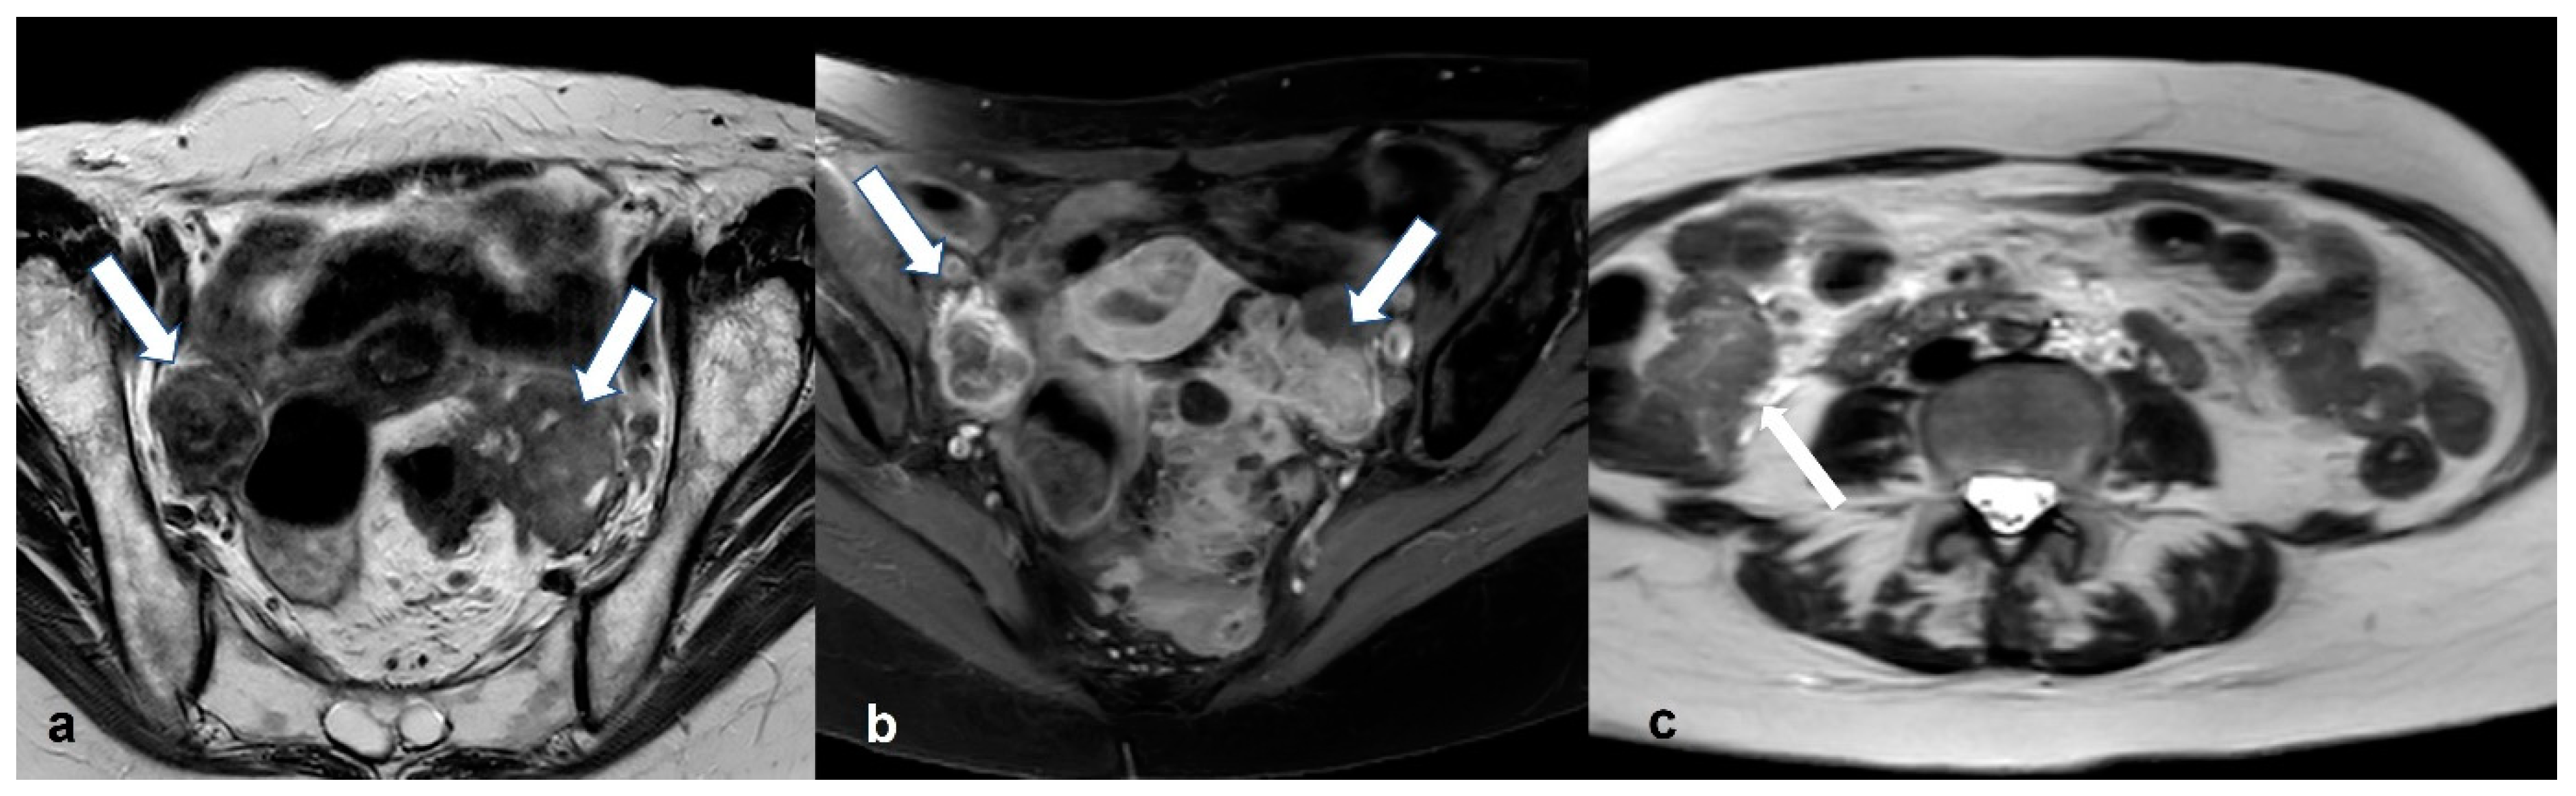

2.2.3. Pelvic Inflammatory Disease—Tubo-Ovarian Abscess (TOA)

2.3. Rare Ovarian Neoplasms That Can Mimic EOC